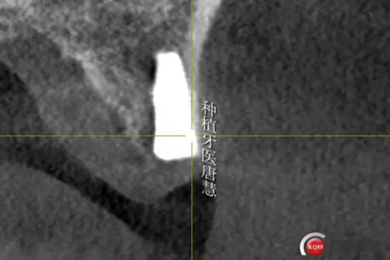

術(shù)后片